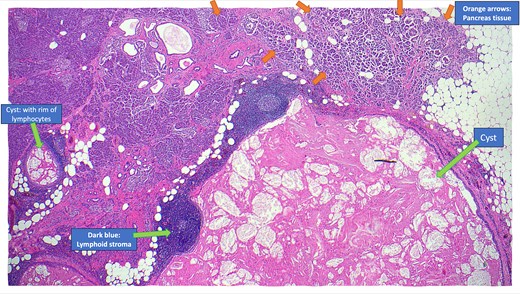

The resected specimen is shown in Fig. 2 and included the distal pancreas and spleen, weighing 202.2 g in total. The pancreas contained a well-circumscribed, lobulated cystic lesion measuring 37 × 27 × 19 mm. The lesion was adjacent to the splenic hilum but did not infiltrate the spleen. The cut surface of the lesion showed multiloculated cystic spaces with tan, necrotic-appearing areas. Histopathological analysis is illustrated in Figs 3 and 4, which confirmed a benign lymphoepithelial cyst. The lesion was clear of all surgical margins, and there was no evidence of malignancy in peri-pancreatic lymph nodes or surrounding tissues.

Annotated haematoxylin and eosin-stained microscopic cross-sectional sample demonstrating atrophic pancreatic parenchyma adjacent to the multilocular cyst with benign lymphoid stroma and reactive lymphoid follicles.